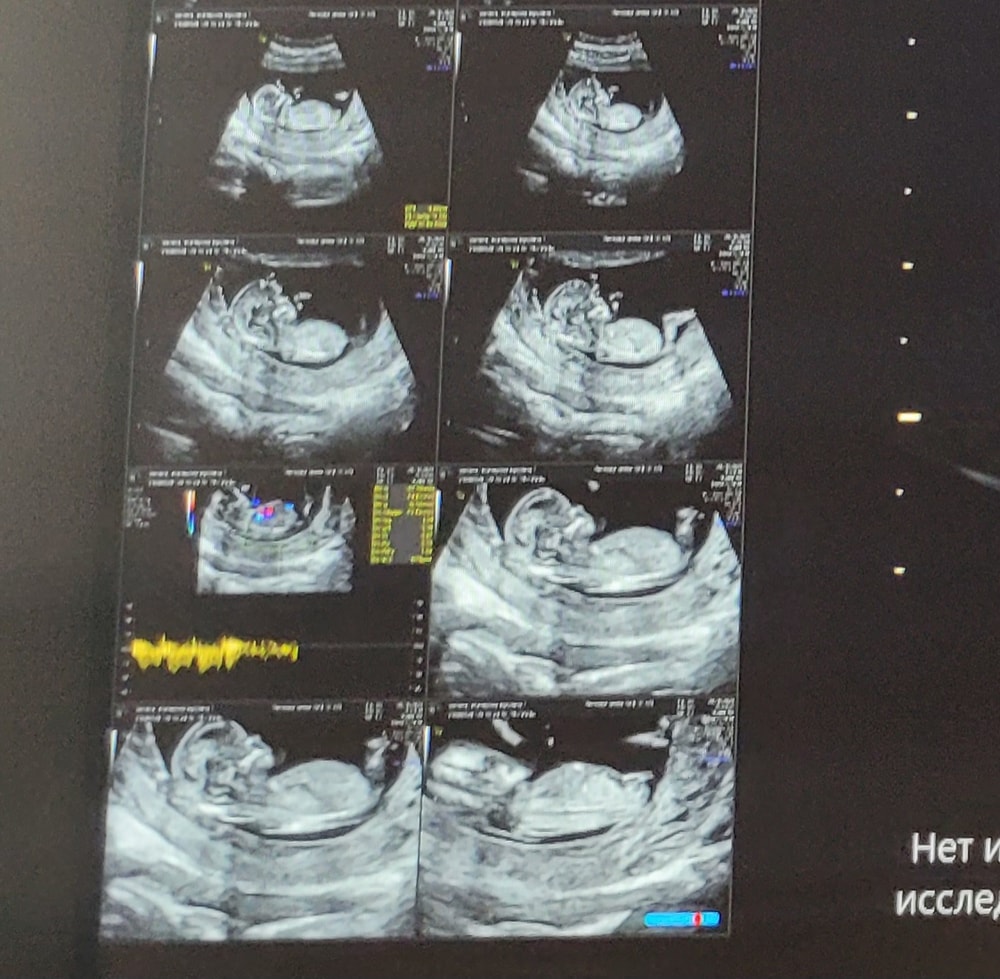

Пол ребёнка по узи в 13 недель

Никогда еще за 3 беременности (2015, 2018 и 2021 г.) мне не говорили пол на первом скрининге. Но сейчас я впервые делала его в новом перинатальном центре. Аппаратура явно отличается от аппаратов в обычных женских консультациях. Врач сказала, что пол неплохо так определяется.

А что видите вы?

Срок 13 недель.

Я не эксперт, но по видео из Ютуба где врач говорит про угол полового бугорка - похоже на девочку:) если то, что я думаю это половой бугорок у вас на снимке, а не пуповина или нога😃